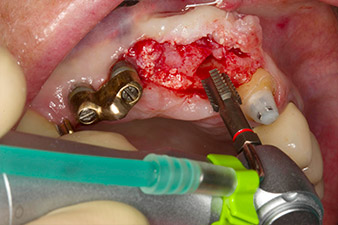

pilot drilling is performed with the new Implantmed and the WS-56 L contra-angle handpiece

Fig. 2: Two months later the pilot drilling is performed with the new Implantmed and the WS-56 L contra-angle handpiece (programme P1, ratio 1:1). The cooling is performed via the spray tube positioned on the left (for right-handed users).

Following primary healing, the soft tissues were shaped using the basally lined bridge. Two months later the site was exposed by a slightly palatal alveolar ridge incision (Fig 2). The dimensions of the alveolar bone proved to be sufficient at position 22. Figures 2 and 4 show the preparation of the implant bed, the tapping and the implantation using Implantmed.